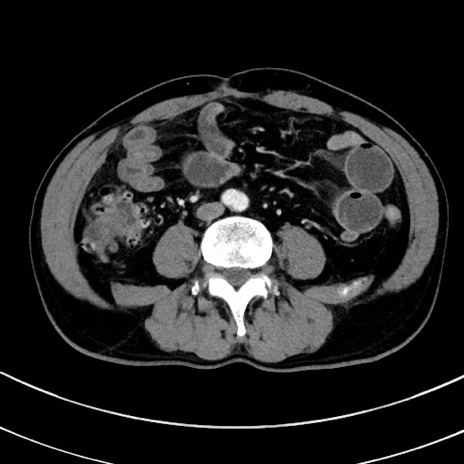

症例8(横断像)

【症例】 60歳代男性

【主訴】 黒色吐物

【現病歴】 4日前から嘔気自覚、2日前の朝食後にも嘔気あり、自分で手で嘔吐反射起こし嘔吐したところ血が混ざっていたため受診。

【既往歴】 5年前汎発性腹膜炎を伴う急性虫垂炎で手術、高血圧、前立腺肥大症、高脂血症

【身体所見】 腹部正中に手術癩痕あり 腹部平坦・軟圧痛なし膨満感あり

【データ】WBC 8400、CRP 4.54